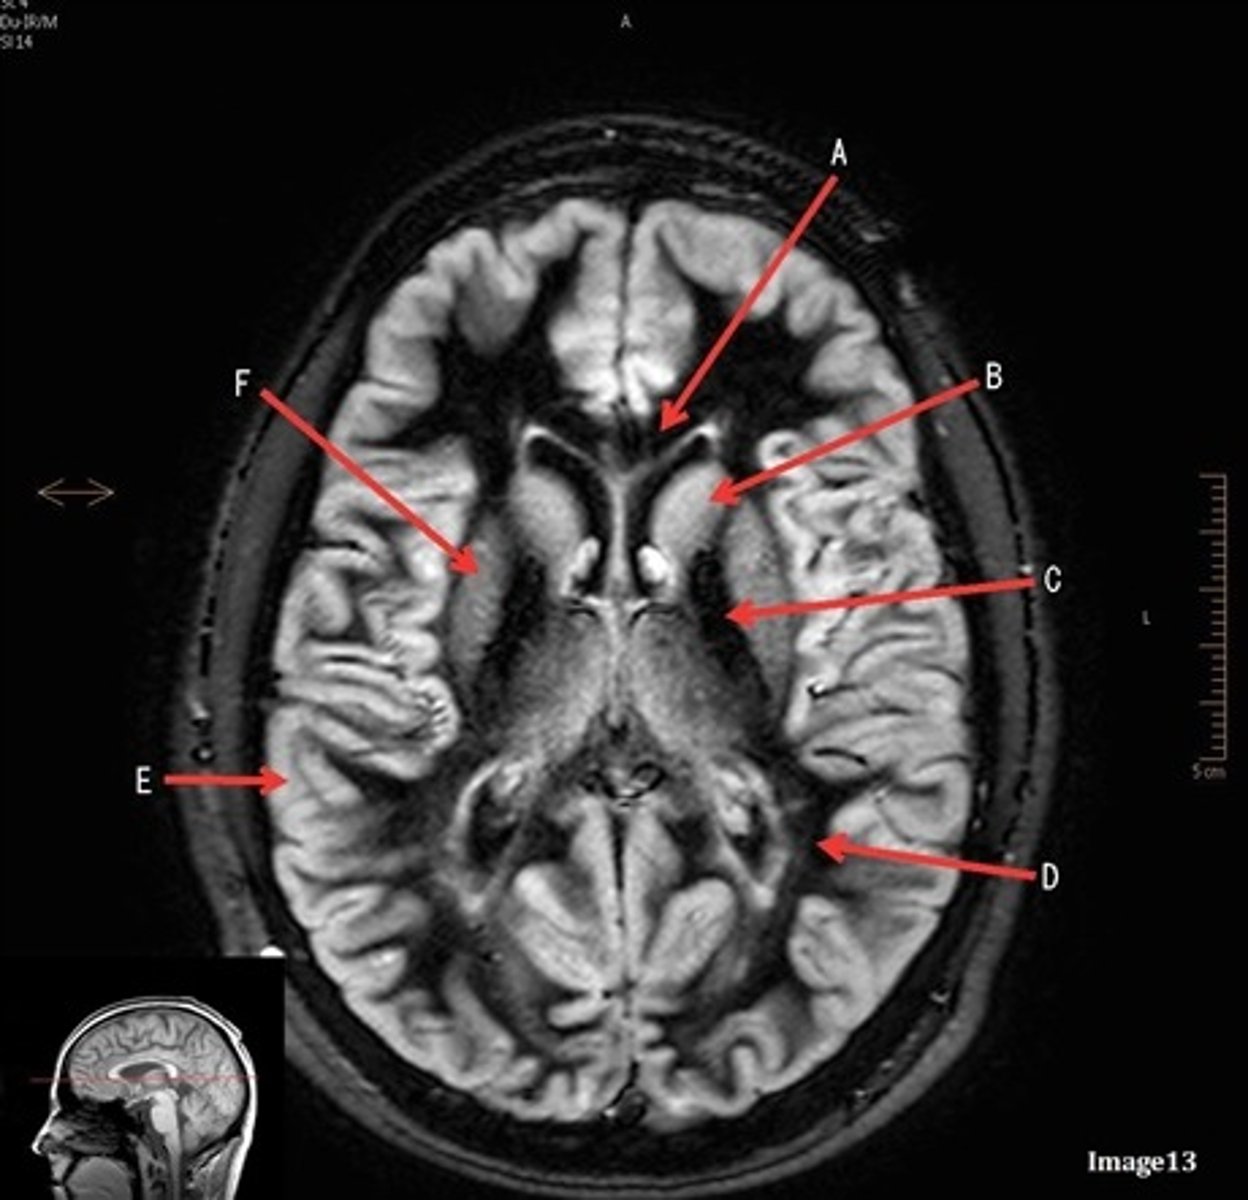

A

A- anterior cerebral artery

B

B- internal carotid artery

C

c- vertebral artery

D

D- basilar artery

E

E- posterior cerebral artery

F

F- middle cerebral artery